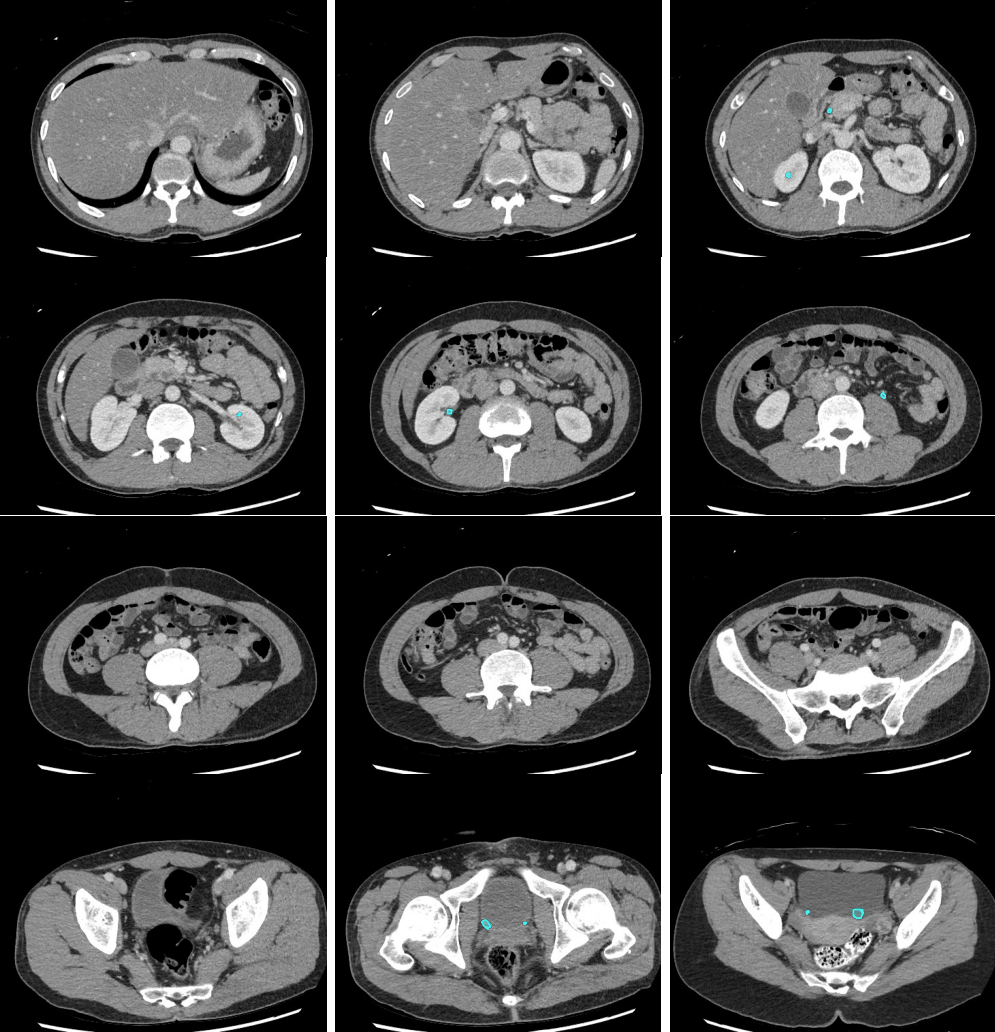

- Look for filling defects in the vessels. Venous enlargement might indicate acute thrombus and confirming increased density by applying tight windows to potentially detect acute venous thrombus can be useful.

Slice 1

Slice 2

Slice 3

Slice 4

Slice 5

Slice 6

Slice 7

Slice 8

Slice 9

Slice 10

Slice 11

Slice 12